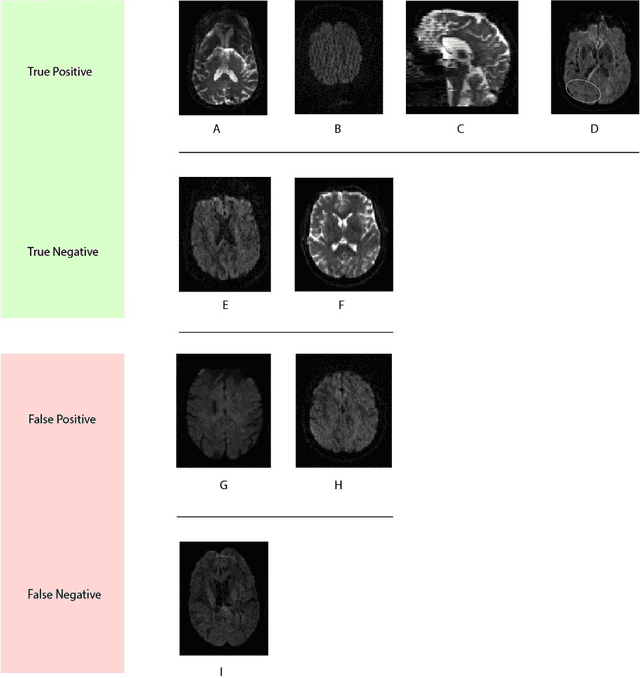

Artifacts are a common occurrence in Diffusion MRI (dMRI) scans. Identifying and removing them is essential to ensure the accuracy and viability of any post processing carried out on these scans. This makes QC (quality control) a crucial first step prior to any analysis of dMRI data. Several QC methods for artifact detection exist, however they suffer from problems like requiring manual intervention and the inability to generalize across different artifacts and datasets. In this paper, we propose an automated deep learning (DL) pipeline that utilizes a 3D-Densenet architecture to train a model on diffusion volumes for automatic artifact detection. Our method is applied on a vast dataset consisting of 9000 volumes sourced from 7 large clinical datasets. These datasets comprise scans from multiple scanners with different gradient directions, high and low b values, single shell and multi shell acquisitions. Additionally, they represent diverse subject demographics like the presence or absence of pathologies. Our QC method is found to accurately generalize across this heterogenous data by correctly detecting 92% artifacts on average across our test set. This consistent performance over diverse datasets underlines the generalizability of our method, which currently is a significant barrier hindering the widespread adoption of automated QC techniques. For these reasons, we believe that 3D-QCNet can be integrated in diffusion pipelines to effectively automate the arduous and time-intensive process of artifact detection.